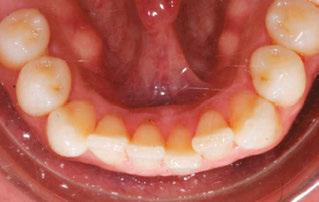

Figure 2: Initial lower occlusal

This case involves a 13-year-old female patient with a complex malocclusion that includes multiple dental and skeletal issues. During the initial consultation, clinical evaluation showed severe maxillary crowding along with generalized spacing in the mandibular arch. The patient’s occlusal relationships were asymmetric, with a Class I molar relationship on the right side and a Class II molar relationship on the left. Notably, an anterior crossbite was observed, further complicated by a narrow, V-shaped maxillary arch — a common presentation that often exacerbates anterior-posterior discrepancies and limits functional occlusion. The patient also demonstrated poor oral hygiene, which is a key indicator of an indirect bonding system that does not reduce excess flash. ODB is superior in flash reduction, by being able to remove excess adhesive from three sides of the bracket instead of competitors who only remove adhesive from one side of the bracket. The presence of adhesive around brackets contributes to surface roughness which leads to plaque accumulation.1 Flash reduction will be very important for every patient’s orthodontic success (Figures 1-3).